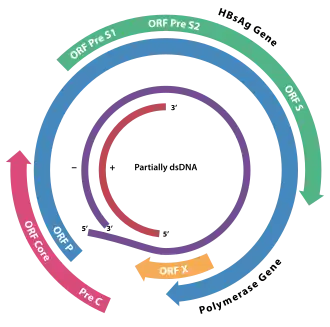

HBsAg (also known as the Australia antigen) is the surface antigen of the hepatitis B virus (HBV). Its presence in blood indicates existing hepatitis B infection.

The full-length HBsAg is called the L (for "large") form. It consists of a preS loop, a first transmembrane helix (TM1), a cytosolic loop (CYL), another TM helix (TM2), an antigenic loop (AGL), followed by two TM helices (TM3 and TM4). The preS loop can either be on the outside (lumen), or be located in the cytosol with the TM1 helix not actually penetrating the membrane. The M ("medium") form has a truncated preS; the part of preS1 unique to L is called preS1, while the part shared by L and M is called preS2. preS2 is always located in the lumen. The S ("small") form has no preS2.[1]

HBsAg forms the shell of the virus. Furthermore, it contains parts that are recognized by the cellular receptor of the virus NTCP in preS1, which causes the causes the virus to tightly bind to the cell. How the virus convinces the cell to take the virus in after binding via endocytosis is unknown.[2] It also serves to release the contents of the virion into the cell through membrane fusion. The part responsible for fusion is also located in preS1.[3]

HBsAg self-assembles into viral shells even when no contents are present. Such an empty shell is called a virus-like particle or a small spherical subviral particle.[1]